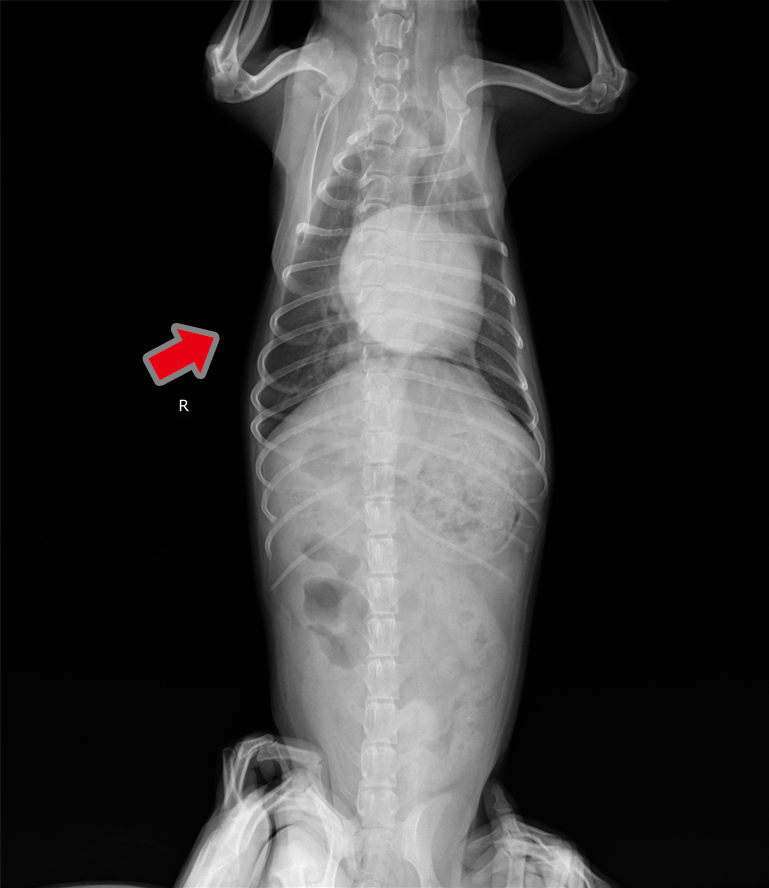

- 肺水腫(治療前)

- 肺水腫(治療後):肺(矢印)が白から黒へ改善